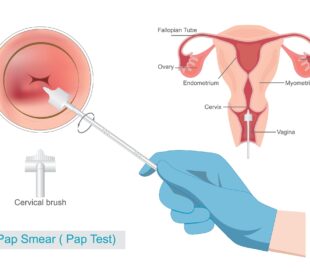

Gimdos kaklelio vėžys yra viena iš dažniausių moterų onkologinių ligų, kuri ankstyvose stadijose dažniausiai nesukelia jokių simptomų. Dėl to profilaktiniai ginekologiniai tyrimai ...Kaip nustatomas prostatos vėžys